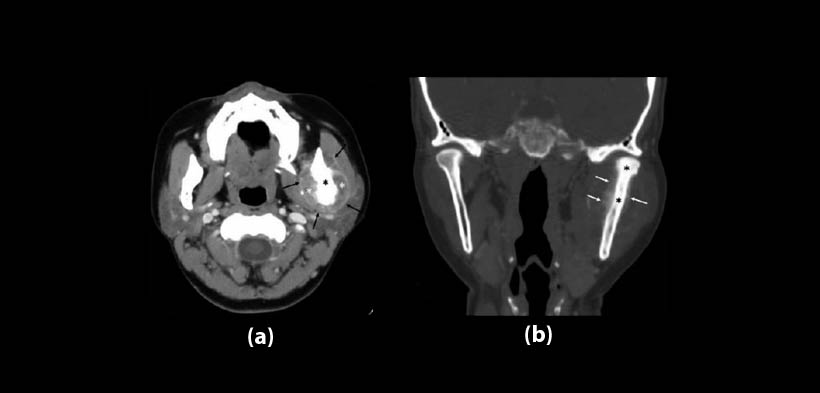

Fig. 2 Osteosarcoma en una mujer de 41 años de edad. (a) TC post-contraste, vista axial, muestra un masa osteoblástica de tejido tumoral (asterisco negro) a nivel de la rama mandibular izquierda con una extensión hacia los tejidos blandos (asteriscos blanco) y realce periférico (flechas negras). (b) TAC, reconstrucción multiplanar, vista coronal, muestra una alta densidad dentro de la cavidad medular de la rama izquierda mandibular y del cóndilo (asteriscos negro) en comparación con el lado opuesto, se evidencia también la reacción perióstica (flechas blancas)